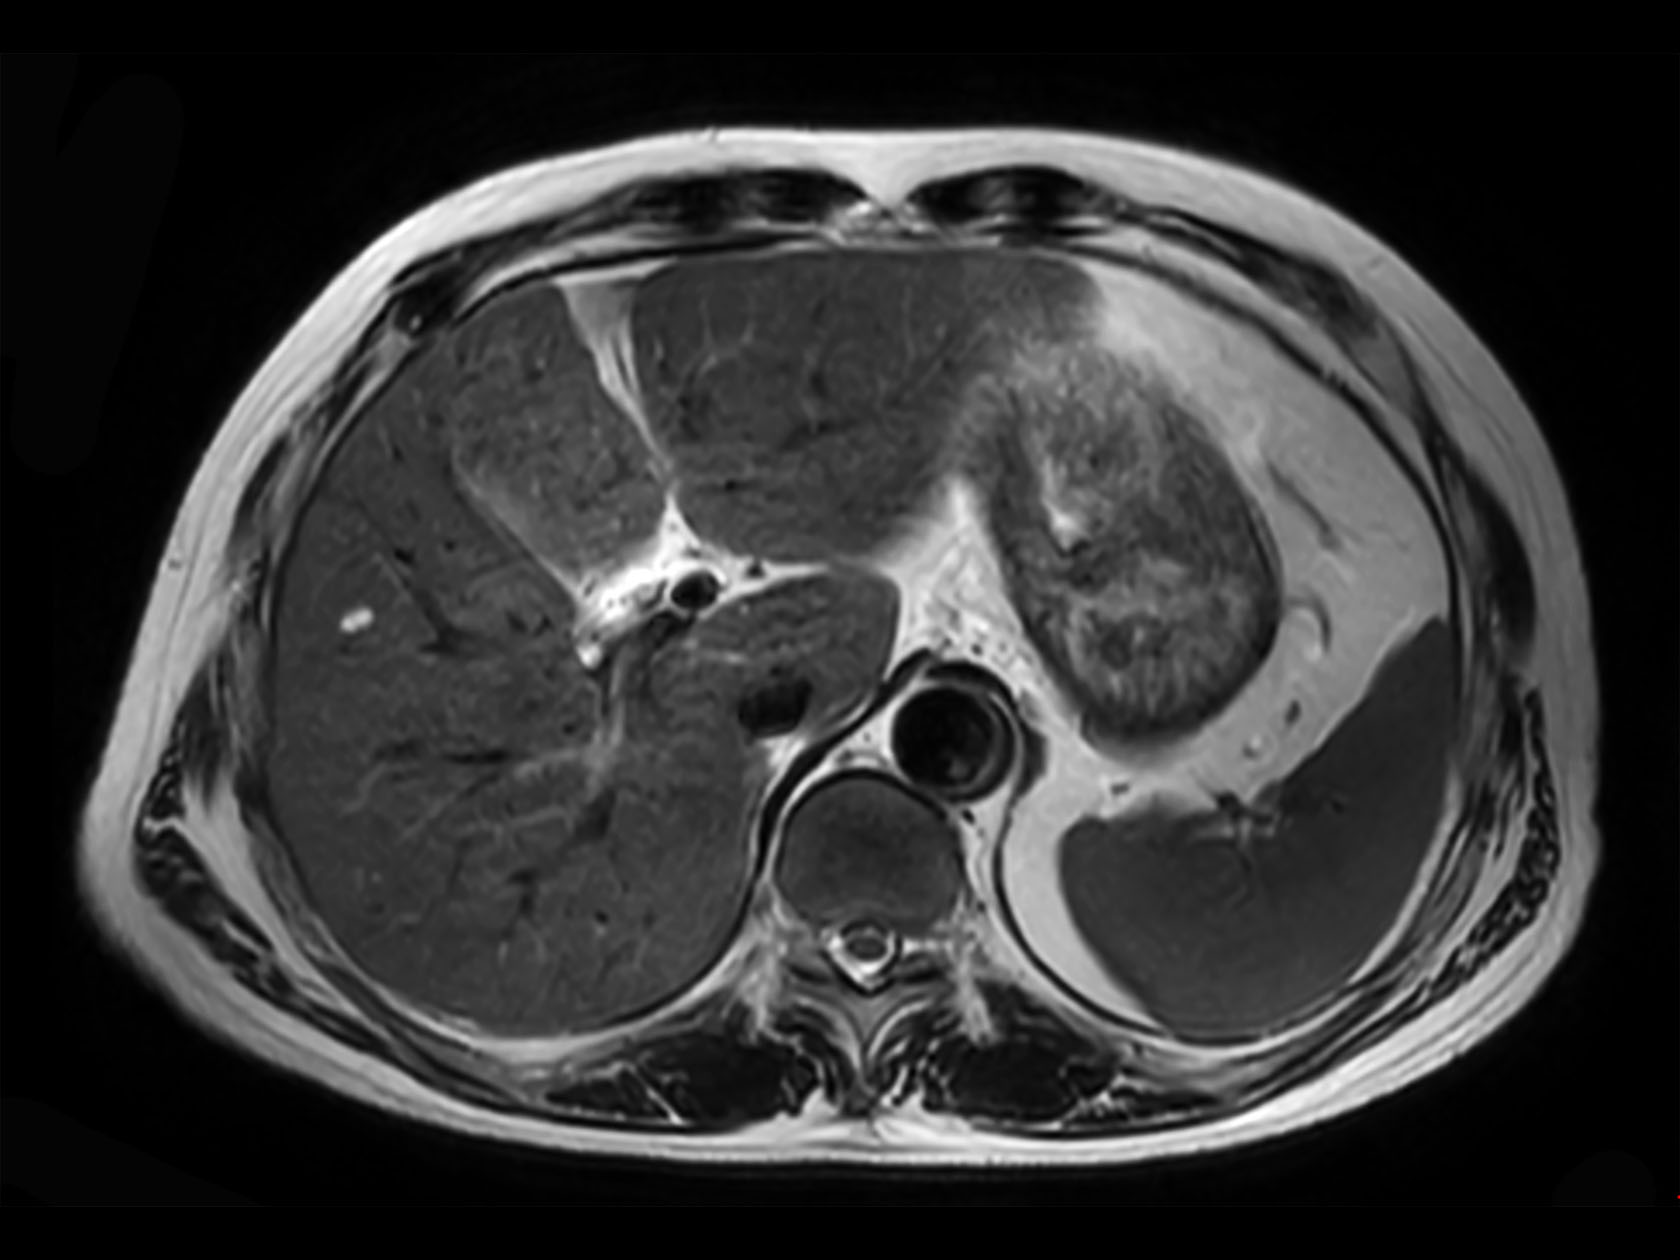

Axial 3D VANE XD (In Phase)